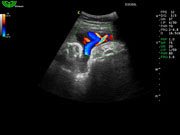

Система поддерживает СFM-режим, PW-режим, CW-режим, режим направленного энергетического потока, режим Color-M, панорамный режим, ECG, DICOM 3.0 и универсальные пакеты программ для кардиологии, сосудистого исследования и акушерства.

Режимы изображения: B, 2B, B/M, B/BC, CFM, PW, HPRF, PD, направленный PD, CW, режим Color M.

Дополнительные возможности: триплекс, трапециидальное отображение, анатомический М-режим, «free-hand» трехмерная реконструкция, авто-доплер.